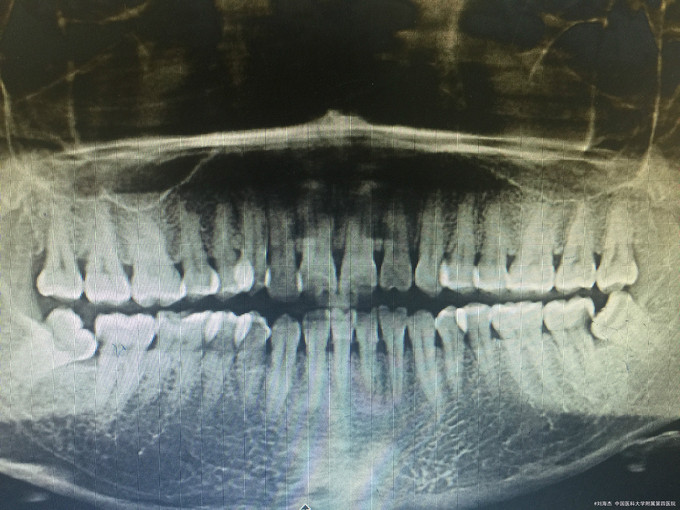

临床检查:37远中邻面龋坏,探疼(+),冷(++),叩(-),松动度(-),牙周正常. 38阻生齿未完全萌出。 辅助检查:X线示37龋坏累积髓腔,38近中阻生。

诊断:37牙髓炎,38阻生齿。 治疗:经患者知情同意后,37局麻去腐降牙合,开髓拔髓寻找根管口,建立直线通路,扩通根管,确定工作长度。vdw/EDTA凝胶镍钛器械,低浓度次氯酸钠冲洗根管,预备至25/06,氢氧化钙诊间封药,一周后复诊,试主尖X线示恰充,试干根管,导AH-PLUS糊剂,VDW热压胶垂直加压根充,术后见根管恰充,暂封调合抛光。择期拔除38.